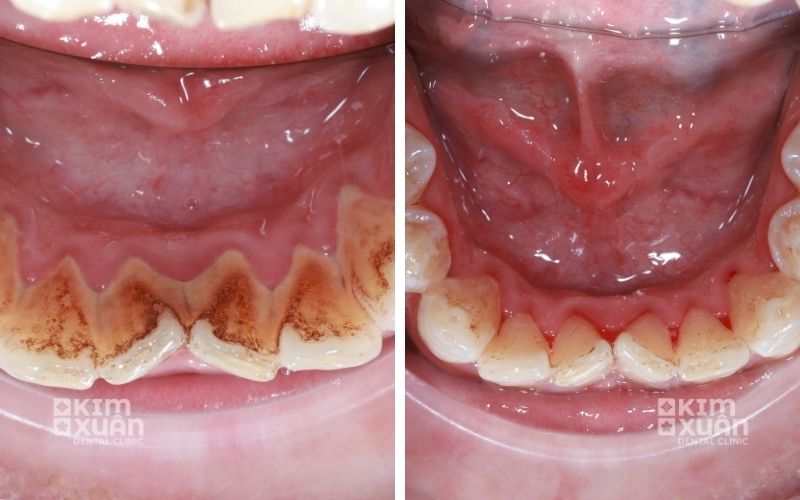

6.1. Cạo vôi răng - làm sạch chuyên sâu

Bác sĩ sẽ tiến hành lấy sạch mảng bám và cao răng bám quanh chân răng và dưới viền nướu. Đây là bước quan trọng giúp giảm viêm, hạn chế vi khuẩn và tạo điều kiện để nướu phục hồi khỏe mạnh.